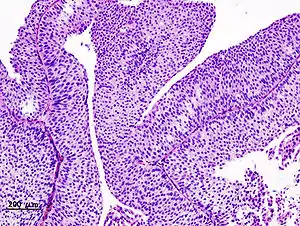

| تصویر بافتشناختی از مخاط سرطانیشدهٔ مثانه | |